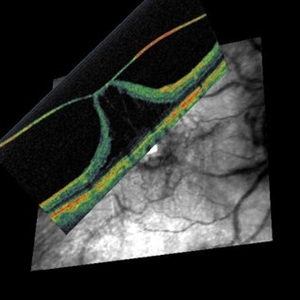

Vitreo-Macular Traction Syndrome

Combined OCT and Scanning laser ophthalmoscopy demonstrate separation of full-thickness posterior vitreous cortex (no vitreoschisis), but persistent adhesion centrally with significant detachment of the fovea. [from Sebag J: Vitreous – in Health & Disease (J. Sebag, ed.) Springer, New York, 2014; image © Springer Nature, reprinted with permission]

Condition/keywords: vitreomacular traction (VMT)